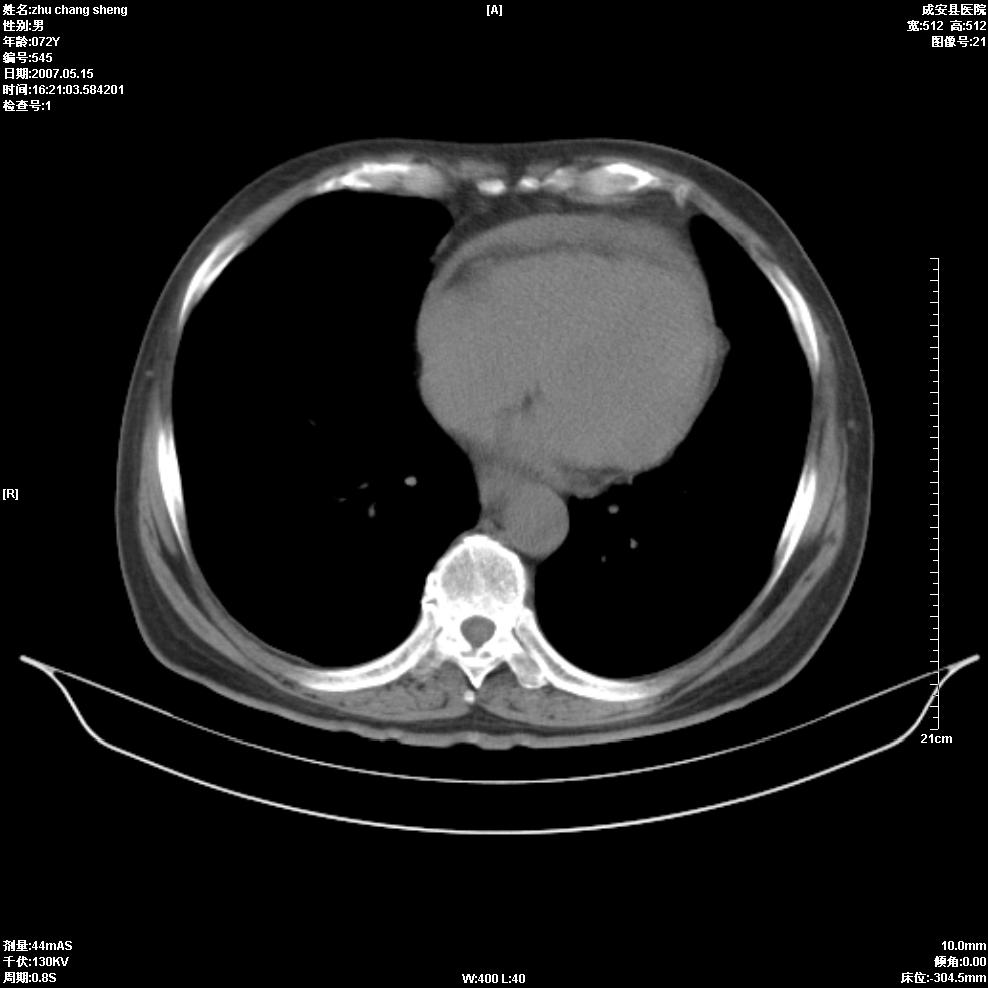

以下是引用医博云天在2007-5-15 19:10:00的发言:[br]心包积液,胸腔积液,心影增大,左心为主。

以下是引用zhangzhongshou在2007-5-15 20:21:00的发言:[br]心包积液可以肯定有,肿块显示不清,建议增强或mri检查。

以下是引用jinning在2007-5-15 21:06:00的发言:[br]心包积液可以肯定,建议增强或mri检查吧!

以下是引用拾荒者在2007-5-15 22:28:00的发言:[br]心包膜增厚,有少量积液,右室前壁示均匀软组织密度影,边界欠清,建议增强扫描或mri检查与室壁瘤鉴别。

以下是引用还珠格格在2007-5-19 9:50:00的发言:[br]病人与5月18日 做了核磁增强扫描 确诊为前上纵隔侵袭性胸腺瘤。